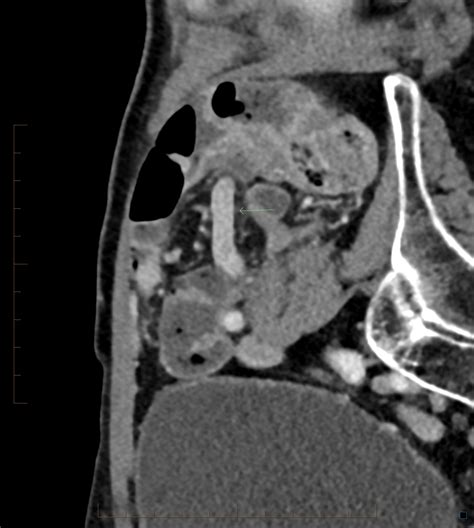

• Appendix Diameter: A normal appendix is typically 6 millimeters or less in diameter. If the diameter exceeds this threshold, it is a primary indicator of distention and inflammation.

• Periappendiceal Fat Stranding: This appears as hazy, gray density surrounding the appendix, indicating that the inflammation has begun to spread into the surrounding fatty tissue.

• Extraluminal Fluid: The presence of free fluid around the appendix or in the pelvic cavity suggests that the appendix may be perforated or severely inflamed.

Once the radiologist identifies appendicitis on CT, the clinical path becomes much clearer. The scan helps the surgical team determine whether the condition is simple or complicated. A simple appendicitis is characterized by inflammation without rupture. A complicated appendicitis, on the other hand, might show signs of an abscess, perforation, or localized peritonitis.